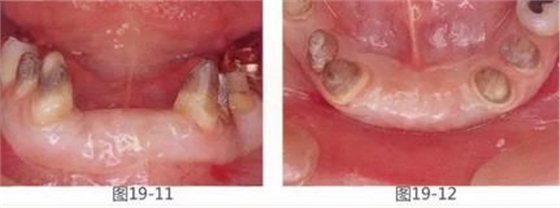

圖19-11 FGG后4個月的狀態(tài)。牙體周圍獲得了充分寬度的附著齦。

圖19-12 同時期的咬合面照。與圖19-2相比寬度和高度都得到了很好的恢復(fù),提高了橋體部的美觀性,清潔性。